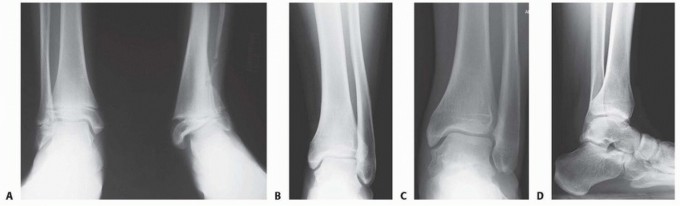

Distal Tibial Osteotomy DEFINITION Angular deformities of the distal tibia can lead to varus or valgus malali…